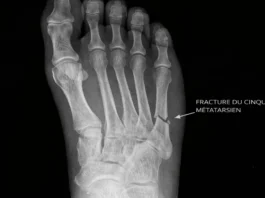

Fractures Métatarsiennes : Identifier et Traiter les Blessures du Pied

Fracture